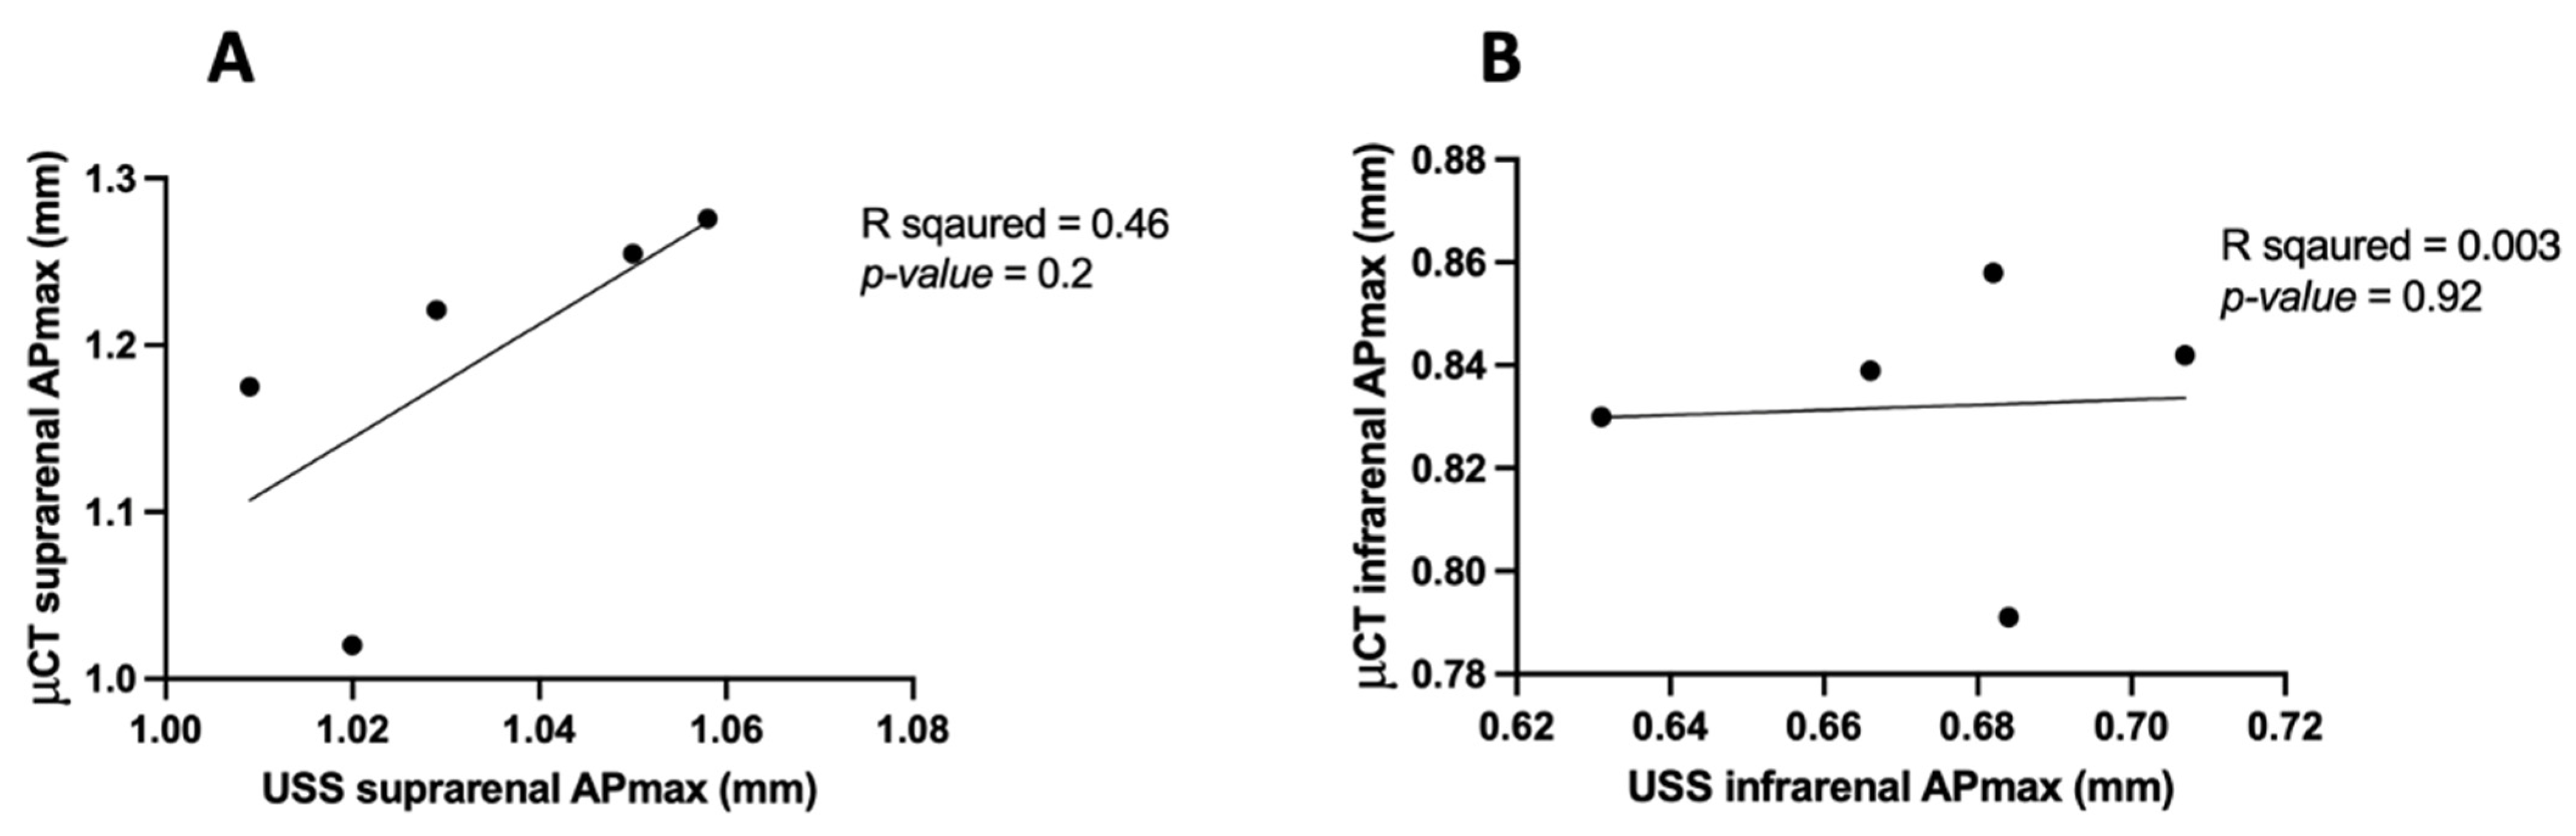

3.3. APmax Inter-Observer and Intra-Observer Variability in μCT

3.3.1. APmax Intra-Observer Variability in μCT

3.3.2. APmax Inter-Observer Variability in μCT

3.4. APmax in USS Intra-Observer Variability

3.5. APmax in μCT vs. USS

| Aortic Region | Measurement Modality | Mean APmax (mm) | Standard Deviation (mm) | Correlation (R2) | p-Value |

|---|---|---|---|---|---|

| Suprarenal Aorta | μCT—Inter Observer | 1.18 | 0.10 | 0.84 | 0.02 |

| μCT—Intra Observer | 1.18 | 0.10 | 0.97 | 0.001 | |

| USS—Intra Observer | 1.03 | 0.02 | 0.86 | 0.02 | |

| Infrarenal Aorta | μCT—Inter Observer | 0.83 | 0.02 | 0.90 | 0.01 |

| μCT—Intra Observer | 0.83 | 0.02 | 0.99 | 0.0002 | |

| USS—Intra Observer | 0.67 | 0.02 | 0.82 | 0.03 |